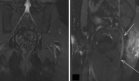

Las imágenes por resonancia magnética preoperatoria revelaron una lesión perihepática multiquística, de 4 × 4,5 × 4,1 cm, con características hipointensas en T1 e hiperintensas en T2, sin alteraciones significativas en la secuencia dual. Se reportó, además, un engrosamiento nodular del hemidiafragma derecho con realce en T1, sugestivo de endometriosis.

La tomografía computarizada confirmó una masa subdiafragmática derecha en íntima relación con la cúpula hepática, grasa pericárdica y fascia lateroconal, con hallazgos sugestivos de enfermedad peritoneal. El PET-CT evidenció hipermetabolismo periférico irregular en la lesión subfrénica, y múltiples focos hipermetabólicos en el diafragma, peritoneo y asas intestinales, compatibles con proceso inflamatorio, probablemente endometriósico.